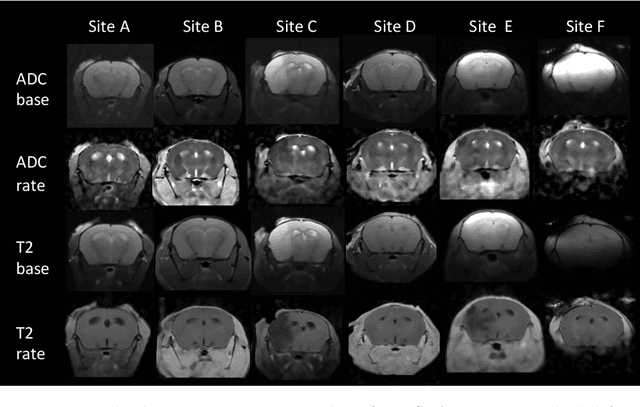

Abstract:Rodent stroke models are important for evaluating treatments and understanding the pathophysiology and behavioral changes of brain ischemia, and magnetic resonance imaging (MRI) is a valuable tool for measuring outcome in preclinical studies. Brain extraction is an essential first step in most neuroimaging pipelines; however, it can be challenging in the presence of severe pathology and when dataset quality is highly variable. Convolutional neural networks (CNNs) can improve accuracy and reduce operator time, facilitating high throughput preclinical studies. As part of an ongoing preclinical stroke imaging study, we developed a deep-learning mouse brain extraction tool by using a U-net CNN. While previous studies have evaluated U-net architectures, we sought to evaluate their practical performance across data types. We ask how performance is affected with data across: six imaging centers, two time points after experimental stroke, and across four MRI contrasts. We trained, validated, and tested a typical U-net model on 240 multimodal MRI datasets including quantitative multi-echo T2 and apparent diffusivity coefficient (ADC) maps, and performed qualitative evaluation with a large preclinical stroke database (N=1,368). We describe the design and development of this system, and report our findings linking data characteristics to segmentation performance. We consistently found high accuracy and ability of the U-net architecture to generalize performance in a range of 95-97% accuracy, with only modest reductions in performance based on lower fidelity imaging hardware and brain pathology. This work can help inform the design of future preclinical rodent imaging studies and improve their scalability and reliability.

Abstract:Ischemic stroke is a leading cause of death worldwide, but there has been little success translating putative cerebroprotectants from preclinical trials to patients. We investigated computational image-based assessment tools for practical improvement of the quality, scalability, and outlook for large scale preclinical screening for potential therapeutic interventions. We developed, evaluated, and deployed a pipeline for image-based stroke outcome quantification for the Stroke Prelinical Assessment Network (SPAN), which is a multi-site, multi-arm, multi-stage study evaluating a suite of cerebroprotectant interventions. Our fully automated pipeline combines state-of-the-art algorithmic and data analytic approaches to assess stroke outcomes from multi-parameter MRI data collected longitudinally from a rodent model of middle cerebral artery occlusion (MCAO), including measures of infarct volume, brain atrophy, midline shift, and data quality. We tested our approach with 1,368 scans and report population level results of lesion extent and longitudinal changes from injury. We validated our system by comparison with manual annotations of coronal MRI slices and tissue sections from the same brain, using crowdsourcing from blinded stroke experts from the network. Our results demonstrate the efficacy and robustness of our image-based stroke assessments. The pipeline may provide a promising resource for ongoing preclinical studies conducted by SPAN and other networks in the future.